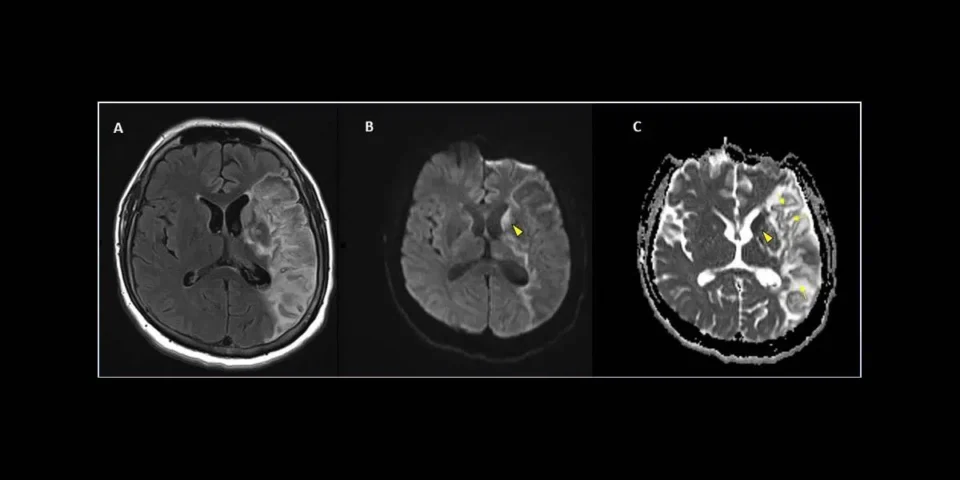

Les décharges épileptiformes frontales ont été proposées comme biomarqueurs du COVID-19. [

Dans notre revue, environ un tiers des patients atteints d’EEG avaient une neuroimagerie anormale. L’incidence plus élevée de neuroimagerie anormale dans notre revue pourrait être due au groupe d’âge plus avancé, à une plus grande proportion d’affections neurologiques préexistantes et à la possibilité que des patients plus malades soient triés pour la neuroimagerie. Plusieurs études ont montré une sensibilité plus élevée pour l’EEG par rapport à la tomodensitométrie cérébrale ou à l’IRM pour l’encéphalopathie liée au COVID-19. Des anomalies de fond, avec ou sans signes d’épilepsie, ont été fréquemment observées chez les patients présentant des symptômes neurologiques lorsque la neuroimagerie était sans particularité. [